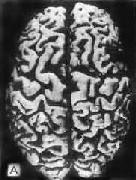

肉眼观,脑萎缩明显,脑回窄、脑沟宽,病变以额叶、顶叶及颞叶最显着(图16-32),脑切面可见代偿性脑室扩张。

图16-32 初老期痴呆的脑

示脑明显萎缩(A),与正常脑(B)的对比